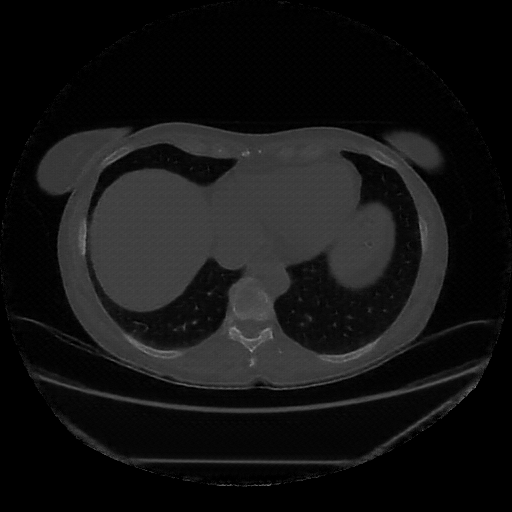

Image Grid

4Γ—3 grid: Rows show different image types (Original NATIVE, Reconstructed NATIVE, Original VENOUS, Generated VENOUS), Columns show windowing techniques (No Window, Lung Window, Mediastinum Window)

Original VENOUS CT scan

Full window (WL 1023.5, WW 4095 β†’ Low βˆ’1024, High +3071)

Lung window (WL -600, WW 1500 β†’ Low βˆ’1350, High +150)